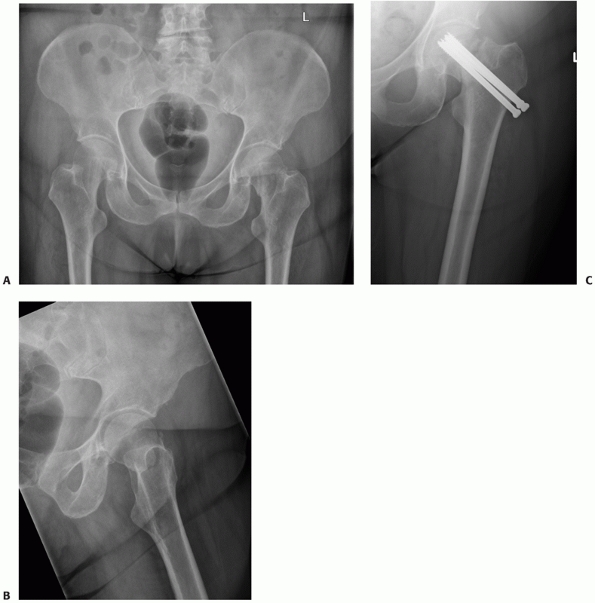

![]() |

|

FIGURE 47-16 A cemented total hip arthroplasty used to treat a femoral neck fracture in a fit older patient.

for displaced intracapsular hip fractures in the past. Total hip

replacement is the most complex operative treatment option for

a

displaced femoral neck fracture. It is a longer operation than the

other operations that have been discussed and, depending on the implant

used, may be the most expensive operative procedure. Many patients who

sustain this injury are not natural choices for total hip arthroplasty

(THA) as most are elderly, have limited mobility, and 25% to 30% have

some degree of cognitive impairment. In addition the initial experience

with THA for intracapsular fractures was not very encouraging. Early

reports detailed high rates of loosening and dislocation.99,100,246 This led to pessimism about the use of THA, and most surgeons are still reluctant to consider it as a treatment option.19

Nonetheless, there is now an accumulating body of evidence that

supports the use of THA in suitable patients, and some recent trials

have indicated that the functional outcome may be more favorable than

other procedures.